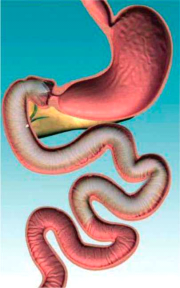

| 12:09, 30 במאי 2013 | EndoBarrier2.png (קובץ) |  |

219 קילו־בייטים | Motyk | 1 | |

| 09:47, 30 במאי 2013 | EndoBarrier1.png (קובץ) |  |

125 קילו־בייטים | Motyk | 1 | |